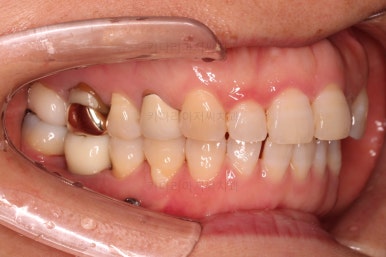

최종 사진을 보여드리겠습니다.

깔끔하게 마무리가 되었네요.

전후 비교입니다.

환자분도 치료에 만족하시어 미적으로 보기싫은 다른 금니들도 하나씩 교체하고 계신 중입니다.